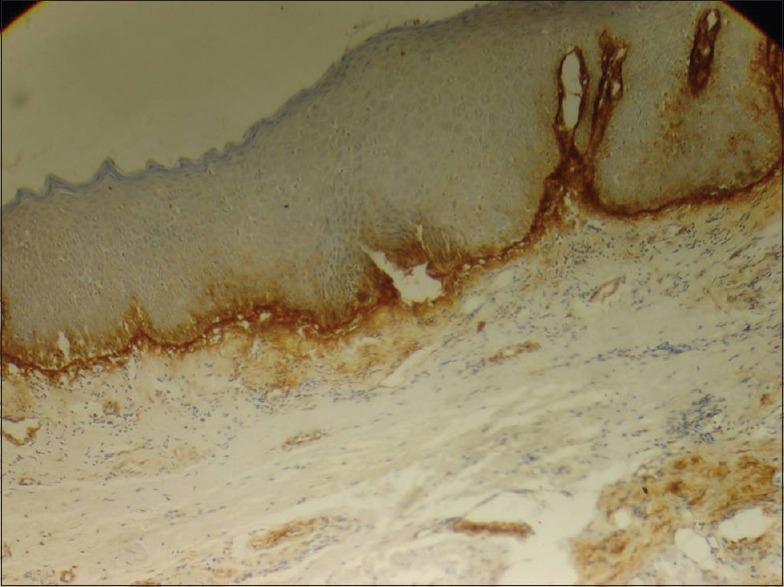

A retrospective cross-sectional immunohistochemical (IHC) analysis of OSMF cases was performed. Total 70 slide samples were prepared for the study from 35 formalin-fixed paraffin-embedded tissue blocks with 10 each from histologically proven and graded as early, moderate and advanced OSMF and 5 of normal oral mucosa. The IHC sections were analyzed for the intensity and pattern of tenascin expression at the junction of epithelium and connective tissue (ECJ) and deeper connective tissue (CT), as well as presence or absence of staining around inflammatory cells, fibroblast and endothelial cells using anti-human tenascin.

Most of the OSMF cases showed retention of antigen at ECJ and in deeper CT. Its expression varied in different grades as well as around inflammatory cells, fibroblast and endothelial cells in same tissue section. Highly significant P values of 0.001 and 0.003 were obtained for tenascin intensity and pattern, respectively, at ECJ in different OSMF grades. In addition, for the expression of tenascin pattern in deeper CT among different OSMF grades, a significant P value of 0.018 was obtained.

A differential expression of tenascin was observed with the progression of disease. The expression of tenascin as bright and continuous deposition at ECJ in early and moderate stages of OSMF signifies either proliferative organization within the overlying epithelium or an epithelial-mesenchymal interaction. However, a weak immunoreactivity of tenascin at ECJ was observed in advanced stage of OSMF.